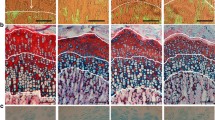

Representative sections of proximal tibial growth plates of control (C; a) and rapamycin-treated (RAPA; b–e) animals stained with alcian blue/safranine. Details of proliferative zone of RAPA proximal tibial growth plates (c), hypertrophic zone of RAPA proximal tibial growth plates (d), and metaphyseal front of RAPA proximal tibial growth plates (e). Magnification bars: 100 μm

Periodic acid-Schiff (PAS) reaction in the proximal tibial growth plate of control (C; a) and rapamycin-treated (RAPA; b) animals. Cytoplasmic glycogen deposits in control rats are shown at greater augmentation. Magnification bars: 100 μm

Von-Kossa staining showing matrix mineralization of proximal tibial growth plates of control (C; a) and rapamycin-treated (RAPA; b) animals. Magnification bars 100 μm

Histology and histomorphometry of the growth cartilage

Heights of both the growth cartilage and its hypertrophic zone greatly varied in RAPA animals, sometimes being greater than in C animals (Fig. 2a,b). The histomorphometric analysis did not demonstrate significant differences in either the height of epiphyseal cartilage (C: 493 ± 32 μm; RAPA: 629 ± 47 μm) or the height of the hypertrophic zone (C: 347 ± 28 μm; RAPA: 437 ± 38 μm).

Even in a context of evident morphological variability, some histological features were consistently present in most samples from RAPA animals (Fig. 2b–e). The proliferative zone was frequently disorganized, with loss of the normal columnar pattern. Acellular regions of fibrinous material markedly stained with alcian blue were often found in this zone (Fig. 2c). The transition between proliferative and hypertrophic zones was sometimes ill defined; others were quite abrupt (Fig. 2b–c). Groups of flattened hypertrophic chondrocytes, with their long axis oriented perpendicular to the longitudinal axis of the bone, were found near the distal end of cartilage (Fig. 2d). Morphometric analysis revealed that the mean height of terminal chondrocytes was significantly lower in RAPA (26 ± 0 μm) than in C animals (29 ± 0 μm). The chondro-osseous junction in RAPA samples was not as neat and regular as in C animals, with zones distorted by clusters of hypertrophic chondrocytes extending into the depth of the primary spongiosa (Fig. 2e). Isolated chondrocytes were occasionally seen within the metaphyseal bone.

In C animals, PAS-positive cytoplasmic granules were clearly seen in chondrocytes of the upper hypertrophic zone (Fig. 3a), and marked cells were gradually disappearing toward the vascular invasion front. In RAPA samples, chondrocytes containing PAS-positive material were seen in a wider area, including most of the hypertrophic zone, and strongly stained chondrocytes were identifiable near the distal end of the growth cartilage (Fig. 3b). Von-Kossa staining (Fig. 4) revealed that mineralization of cartilage matrix in control animals (Fig. 4a) was mostly confined to longitudinal septa flanked by the last two or three chondrocytes of adjacent columns. In RAPA samples (Fig. 4b), a wider band of mineralized cartilage matrix was seen, mineralization affecting not only to longitudinal septa but also to transversal septa. In this group, chondrocytes were often seen immersed in a mass of mineralized matrix.